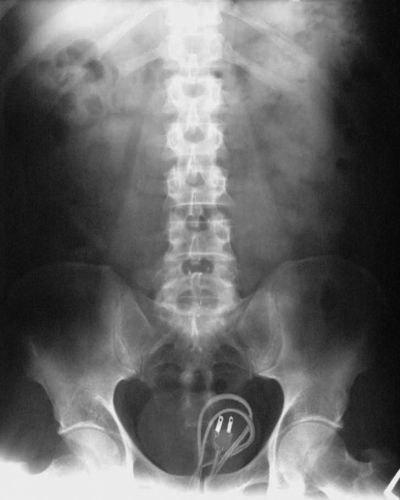

Fios e Cabos Elétricos